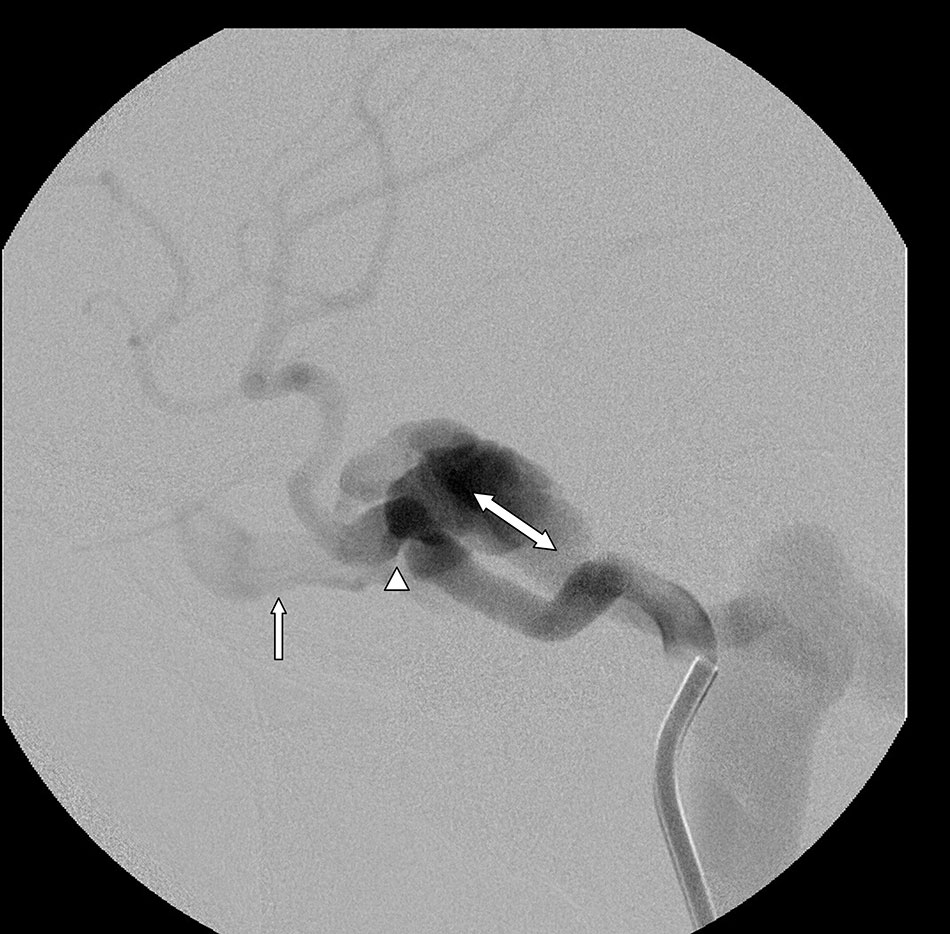

Carotid-cavernous fistulae are a specific kind of dural fistula that involves the carotid artery (or its branches) and a large vein (cavernous sinus) behind the eye. These fistulae can occur because of trauma, if there is an aneurysm in the carotid that breaks and causes the communication, or they can happen spontaneously without a definite reason.

Symptoms can include eye pain, swelling and redness of the eye, double vision or loss of vision if untreated. These fistulae are often treated by an endovascular approach, putting a catheter in the artery or vein, and using material to block up the connection between the artery and vein. This material can include balloons, coils, and liquid glue.